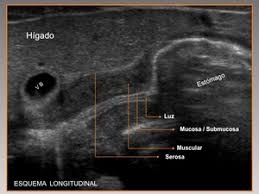

Caracterizada por un engrosamiento anormal del músculo pilórico, lo que lleva a una obstrucción de la salida gástrica. Esta condición es una causa común de vómitos no biliosos en lactantes y generalmente se presenta entre las 2 y 12 semanas de vida.

El diagnóstico se realiza principalmente mediante ecografía, que muestra un alargamiento constante y un engrosamiento de la pared del píloro, con una longitud del canal pilórico superior a 18 mm y un grosor muscular de al menos 4 mm.

Ejemplos de estenosis pilorica hipertrofica infantil.